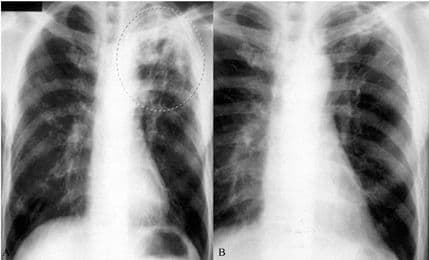

Infekcije tuberkuloze posebno je teško utvrditi kod djece zbog toga što bolest u tom uzrastu izgleda drugačije nego kod odraslih.

Uzrok bolesti je bakterija koja napada pluća i širi se ljudskim kontaktom putem iskašljavanja zaražene osobe.

"Kod djece bolest vjerovatno zahvata i druge djelove tijela, ali ne nužno i pluća", kaže Dženkins i dodaje da, iako su pluća zahvaćena, kod djece je manje bakterija pa se teže "ulove" postojećim metodama dijagnostike.